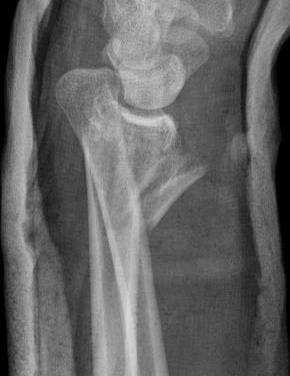

Operative management

Indication

DRUJ instability after distal radius ORIF with ulna styloid fracture

Techniques

Options

Styloid screw

Tension band wire

Ulna hook plate